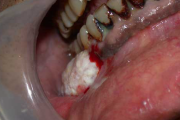

Crohni tõbi